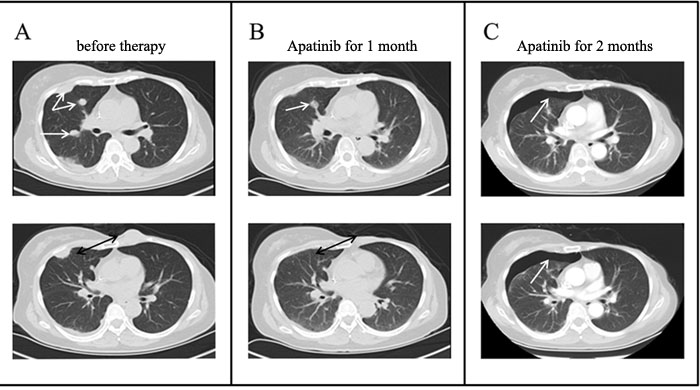

This patient is a 52- year- old woman, who had experienced a benign tumorectomy of left mammary glands 4 years ago. One and a half years ago, she found a lump sized like a peanut kernel in the left breast by chance, which enlarged gradually during the following one month to a lump sized like a common quail egg. Histopathology examination of biopsy sample revealed spindle cell carcinoma by H&E staining (Figure 1A). Subsequently, a modified radical mastectomy had been performed. Histopathology combined with immunohistochemisty results showed a triple-negative (ER/PR/HER2) spindle cell carcinoma (Figure 1). This tumor has a basal epithelial phenotype with expression of high molecular weight cytokeratins 5/ 6, and epithelial marker p63 are also expressed. The spindle-shaped cells are negative for both vimentin and cytokeratin. (Figure 1). These biomarkers also excluded a diagnosis of others spindle cell lesions such as sarcoma. After 6cycles of adjuvant chemotherapy with Cyclophosphamide and Epirubicin, a Positron Emission Tomography/computed tomography (PET-CT) scan was done. It indicated multiple metastases in bilateral lung and left anterior thoracic wall. For obtaining better treatment, she came to our hospital. Physical examination showed consciousness was clear, with poor spirit and chronic faces, no stained yellow on skin and mucous membrane, and no touched swelling of superficial lymph nodes. The patient had got Asthma in 1995 and had no history of hypertension, diabetes, and heart disease. Combining with her tumor history, performance and chemotherapy regimen, we first performed precise diagnosis with genetic testing. The mRNA expression levels of several angiogenesis related genes and classic mutation sites of EGFR were tested by liquid phase chip and ARMS PCR using her surgery sample, which showed a high expression level of Vascular Endothelial Growth Factor Receptor1 (VEGFR1) and a medium expression level of VEGFR2. Moreover, there is no classic mutation of EGFR (Table 1). We then carried out next generation sequencing (NGS) using the same surgery sample, which showed numbers of mutated genes but no matched targeted therapy (Table 2). Aiming at the high VEGFR expression, bevacizumab combined with chemotherapy of Albumin-bound Paclitaxel and Cisplatin was started one week later. Metastatic nodules in lungs became smaller revealed by CT scanning after 3 cycles. However, after another 2cycles, CT scan showed disease progression at all metastatic sites with increased diameters and pleural effusion. Finally, because of the medium expression of VEGFR2, the patient was treated with Apatinib after signing informed consent and confirmed by the hospital ethics committee approval. Before Apatinib therapy, metastatic nodules in the middle lobe of right lung, pleura and left anterior thoracic wall were found by CT scan (Figure 2A). Remarkably, the mass in the left anterior thoracic wall shrank significantly only one week after 500mg/day Apatinib administration. After 1 cycle Apatinib treatment, CT scan showed that the metastatic nodules in pleura, left anterior thoracic wall and bilateral lungs became smaller or almost disappeared. In addition, pleural effusion was improved significantly (Figure 2B).Following an additional one month of Apatinib treatment, pulmonary metastasis further decreased and so as that in pleura and left anterior thoracic wall. It’s worth noting that pneumatothorax appeared because of shrinkage of the pleura lesion, which could be controlled by symptomatic treatment (Figure 2C). To monitor the real-time effect of Apatinib on patient’s gene mutation status, we carried out NGS detection of circulating tumor DNA (ctDNA) from peripheral blood before therapy and after 2 months therapy. The two NGS results were consistent with therapeutic effect, in which number of mutated genes decreased after Apatinib therapy (Table 3). During the therapy, the drug dose was decreased to 250mg/day due to hypertension and hand-foot syndrome until they were totally tolerated. Until now, therapy with Apatinib was continued for 8 months, and the patient was in good general condition after the initiation of Apatinib (data lock, January 2016). The whole timeline of treatment is organized as Figure 3.

Figure 2: Chest CT scans before and after Apatinib therapy. A. CT scans at different layers before Apatinib therapy revealed multiple metastases in right lung, pleura and chest wall; B. After 1 cycle Apatinib treatment, CT scans showed that the metastatic nodules became smaller or almost disappeared; C. After another therapy cycle, pulmonary metastasis further decreased and pneumatothorax appeared at the same site of pleura metastasis.